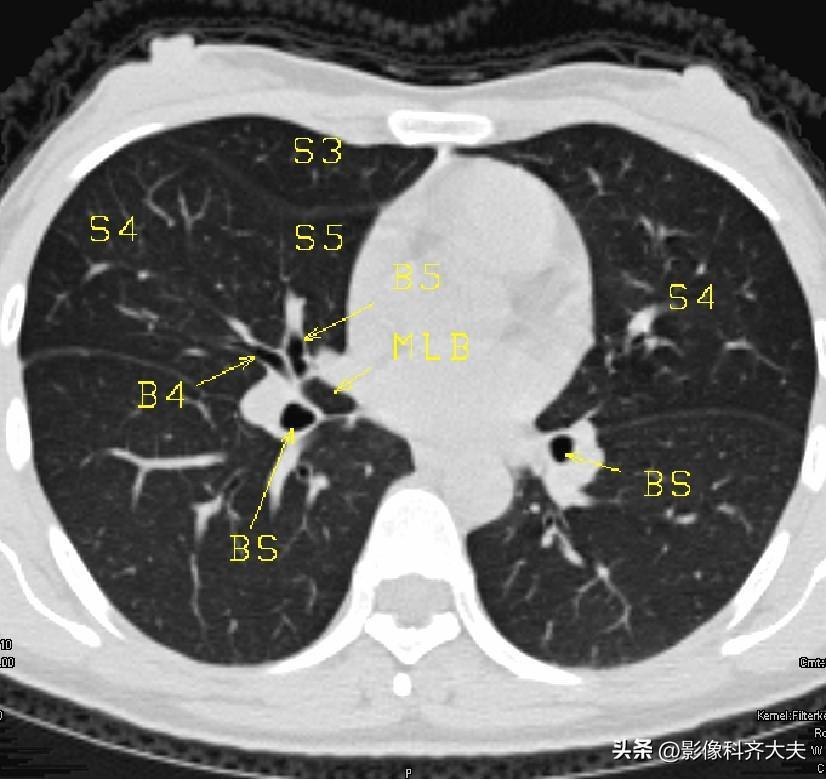

图13

图14

▲B5:右中叶内侧段/左舌下段支气管,BS:基底干支气管,MLB:中叶支气管,S5:右中叶内侧段/左舌下段